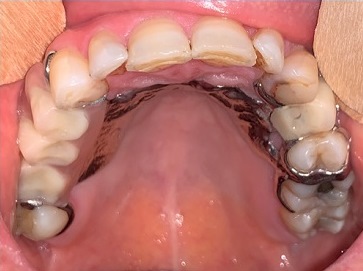

O exame físico revelou um abaulamento assimétrico do hemi‑palato duro esquerdo revelando uma lesão dura, edemaciada e restrita à região edemaciada (Figuras 1 e 2).

Figura 1 Lesão intra‑oral localizada no hemi‑palato duro (com prótese removível esquelética colocada)